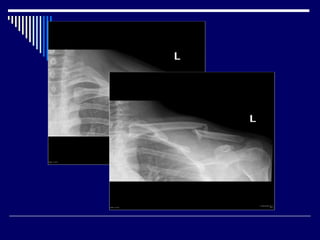

Posterior Shoulder Dislocation

Radiological signs on AP view:

Internal rotation of the humerus

Light bulb sign

The ‘rim sign’ – Widening of the glenohumeral

space

• #18 Several radiological signs have been described on AP view, these include: Light bulb sign – The head of the humerus in the same axis as the shaft producing a light bulb shape Internal rotation of the humerus The ‘rim sign’ – Widening of the glenohumeral space The vacant glenoid sign – Where the anterior glenoid fossa looks empty The ‘trough’ sign – a vertical line made by the impression fracture of the anterior humeral head

• #19 humeral head is forced posteriorly in internal rotation while the arm is abducted . In adults, convulsive disorder is the most common cause. Electrocution is a classic but uncommon cause of posterior shoulder dislocation Posterior dislocation may be missed initially on frontal radiographs in 50% of cases humeral head appears to be almost normally aligned with the glenoid the internally rotated humeral head takes on a rounded appearance known as the lightbulb sign

• #20 AP view of the shoulder demonstrates lack of overlap between the glenoid and the humeral head. The shoulder is rotated such that the humeral head has a 'light bulb' appearance.  glenohumeral joint space - 3-6mm increased - posterior dislocation decreased - degenerative joint disease, crystal arthropathies, inflammatory arthropathies rim sign

• #22 Dislocation film demonstrates no congruency between the glenoid articular surface (blue) and that of the humeral head (yellow). In addition due to internal rotation the proximal humeral head has a rounded appearance, likened to a light bulb (light green). Post reduction film demonstrate the anterior rim of the glenoid (blue) and humeral (yellow) articular surfaces appearing congruent.